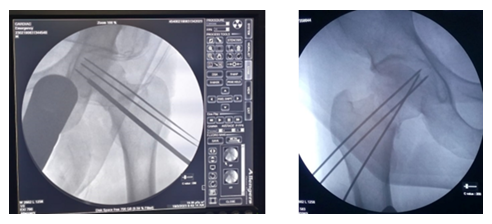

After selecting a case according to inclusion and exclusion criteria, patients were evaluated preoperatively. An elaborate history was taken. This was followed by a general examination and local examination. After admission, patients were put on surface traction to the affected limb with 1/10th of the patient's body weight. All patients underwent preoperative counselling regarding the operative procedure, probable complications, outcome, and other treatment options, along with their merits and demerits. After being informed, written consent was obtained. After preparing the patients for operation, Closed reduction is performed with the patient in the supine position on a fracture table (Figure 1). Reduction was confirmed by C-arm. After reduction, three guide wires are placed, usually in an inverted triangular fashion (Figure 2).

The screw lengths are measured, and drilling is performed using a 4.5 mm cannulated reamer. The screws are then inserted (for the BDSF technique, a specific sequence of middle, then superior, and lastly inferior screw insertion is to be followed). All three screws are inserted less than 5 mm subchondrally (Figure 3,4). In all cases, a prophylactic antibiotic was given. In the postoperative ward, proper fluid and hemodynamic balance were ensured. Change of posture was done twice an hour. The antibiotic was continued for 3 days. Analgesics were given to ensure a pain-free postoperative period. On the first postoperative day, patients were allowed to sit on the side of the bed. Patients were being educated about breathing exercises, isometric quadriceps exercises, gluteal exercises, and ankle pumping exercises. An immediate postoperative X-ray was done (Figure 5). After checking the dressing, on 4th POD, they were discharged from the hospital if their postoperative period was uneventful. Oral antibiotics were given for 10 days. Advice was given to continue isometric quadriceps exercise. Regarding ambulation, they were advised to do non-weight-bearing (of the affected side) crutch ambulation until directed by the physician. Use of elevated toilet seats onwards is also advised. The next follow-up would be given at the 14th POD. The first follow-up was given at 14th POD to check any signs of infection, pain status, and distal neurovascular status. The stitch was removed on the same day. Advice given about isometric quadriceps exercise, active abduction, extension exercise, and stretching exercise of the hip joint. The next follow-up was the 6th week after the operation. The range of motion was tested. An X-ray was done to check callus formation. Improvements were noted. Partial weight bearing was given at this follow-up. Subsequent follow-up was given at 12 weeks and every 4 weeks until union has been achieved or at least 9 months (Figures 6-10).